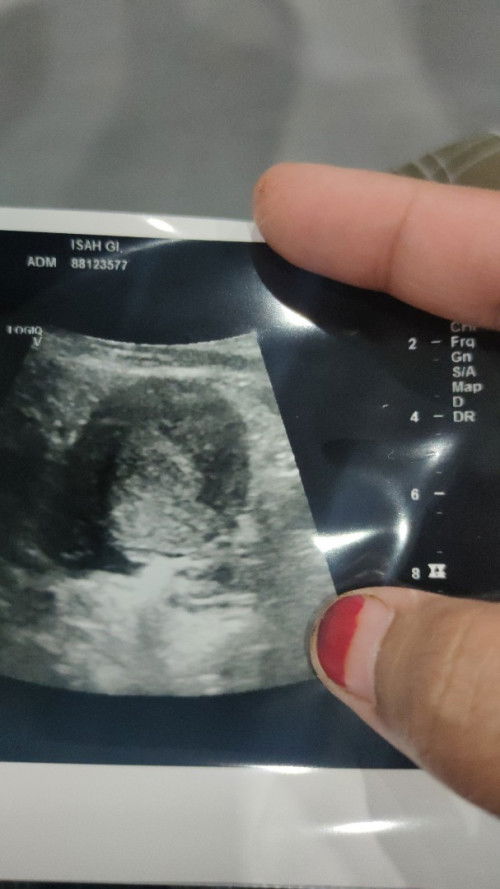

Kenapa ada cecair dalam rahim

Kenapa ada cecair dalam rahim bagaimana cara hilangkan nya ##seriusnanya #pleasehelp #

perlu tgk cycle dan sejarah lain. rahim wanita berubah mgikut cycle. ada masa ia tebal, ada cyst, berair. ada masa ia nipis, kering. perlu tgk medical history mcm mn

samela kite. bru scan pagi td. xtau cecair ape.. klau cyst dktor ckap bulat2. ni hitam panjang..